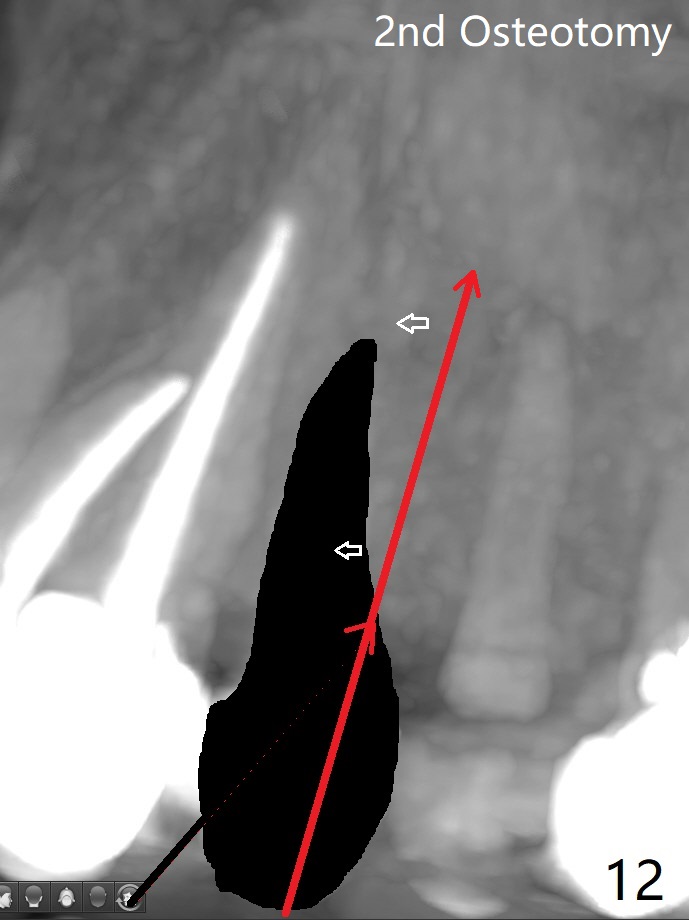

68岁女左上4颊侧瘘道(图一:*),与根尖颊侧骨板缺失相通,其实腭侧根尖周围病变更大(也与颊侧窝相通),术中没有注意腭侧根接近3(图二:P),稀里糊涂的基本顺着腭侧根(颊侧)走向钻洞(图四,与图三理想方向对比),突然记起术前设计钻洞必须在腭侧牙槽窝远中颊侧,在远中建立新洞眼(图五),之后无法再次建立新洞眼,只好利用同一个侧面切割钻头将钻洞往远中移位,同样效果不佳(图六),最后只好放弃,放置粘性骨粉(图七:*),覆盖PRF膜,6个月胶原膜,PGA缝线,牙周胶水。术后重新分析表明顺着腭侧牙槽窝种植与尖牙还是有分离(图八,九:*),因为牙槽窝是斜型的(图十:黑色),不过离颊侧骨板也接近(图八:B)。所以钻洞必须斜型针对远中骨壁,表浅些(图十一:红色箭头);一旦进入骨板,改变角度(图十二:红色箭头),适当矫枉过正,随着植体增大,钻洞会往近中偏移(白色箭头)。最好植体方向理想(图十三)。不过植骨后钻洞偏移可能性比较少。缝线和牙周胶水似乎是一个稳妥固定胶原膜方法。术后病人抱怨水肿严重,术后八天颊侧根尖隆起是由于骨粉推出骨板之外(图十五,十六:*),上颌窦底板无意穿孔(^)伴有上颌窦膜(M)增厚,与术前对比(图十七:上颌窦窦腔清晰)。术后一个月6个月吸收膜不见了,大多数缝线已经脱落,最后两根缝线撤除后,牙槽窝开口已经关闭,好像主要成分是骨粉(图十八)。术后5个月牙槽嵴宽,角化龈也宽,好像可以植入4x11.5毫米植体(图十九)。